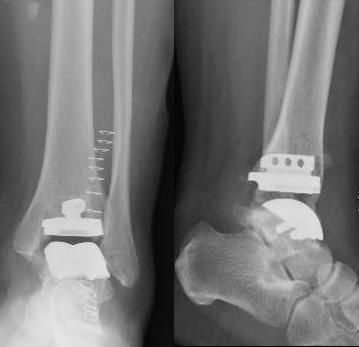

手术进行得非常顺利。术中无需反复透视,截骨精准,假体安放匹配度极高,最大程度保留了健康骨量与软组织。术后X光显示:假体位置良好,下肢力线完美恢复。

术后X线显示人工踝关节假体大小和对合良好,下肢力线良好